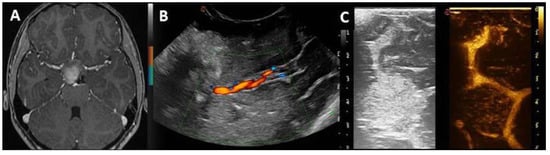

| Pre-IOUS | Problems | Solutions |

|---|---|---|

| Localization | Deep-seated lesion |

|

| Surgical route | Deep-seated lesion |